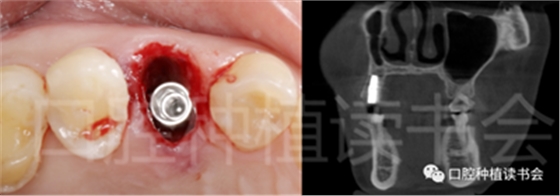

圖1 無法保留的上頜隱裂后牙,拔牙后即刻種植。

后牙區(qū)或者是非美學區(qū)即刻種植,對于患者和臨床醫(yī)生而言,存在一些明顯的優(yōu)勢;比如更小的外科創(chuàng)傷、更短的愈合周期、更少的椅旁時間、更高的患者接受度以及更低的治療費用等。除此之外,在上頜后牙區(qū)即刻種植還可以減少上頜竇的氣化現(xiàn)象【Sharan等.2008】;但并非所有的后牙位點都適合即刻種植,后牙區(qū)即刻種植對醫(yī)生的技術和經(jīng)驗要求更高;由于解剖等諸多條件的差異,美學區(qū)即刻種植的臨床注意事項與后牙區(qū)即刻種植存在諸多不同之處;與本文旨在通過詳細的文獻回顧及臨床案例對后牙區(qū)即刻種植治療提供臨床參考。